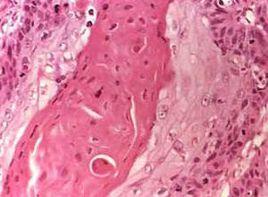

1.肺結核特別是肺結核瘤(球)有時很難與周圍型肺癌相鑑別。肺結核瘤(球)較多見於40歲以下青年病人,病程較長,少見痰帶血,血沉變化少,有16%~28%病人痰中發現結核菌。胸片多呈圓形,見於上葉尖或後段,體積較小,一般不超過5cm直徑,邊界光滑,密度不勻可見鈣化,16%~32%病例可見引流支氣管影指向肺門,較少出現胸膜皺縮,增長慢,如中心液化出現空洞,多居中薄壁且內緣光滑。結核瘤(球)的周圍常有散在的結核病灶稱為衛星灶。周圍型肺癌多見於40歲以上病人,痰帶血較多見,痰中癌細胞陽性者達40%~50%。X線胸片腫瘤常呈分葉狀,邊緣不整齊,有小毛刺影及胸膜皺縮,生長較快。在一些慢性肺結核病例,可在肺結核基礎上發生肺癌,因此在慢性肺結核的成年病人,如果肺部出現異常團塊陰影,肺門陰影增多或經正規抗結核藥物治療後,病變不見吸收好轉反而增大時,都應懷疑肺癌的可能性。必須進一步做痰液細胞學和支氣管鏡檢查,必要時施行剖胸探查術。